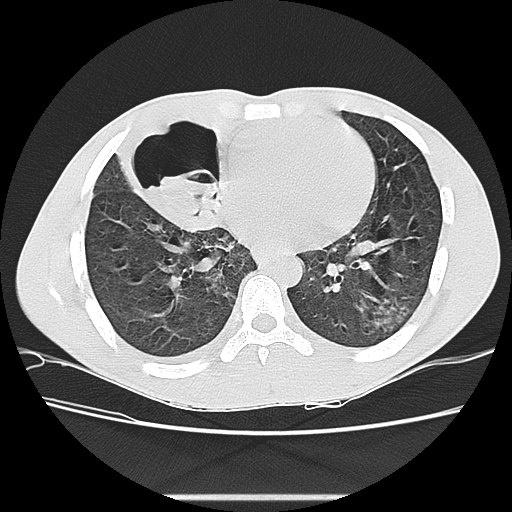

- Эозинофилия, кашель, бронхоспазм, возможны очаговые изменения в легких на КТ.

- Рентгенография и КТ легких (кисты, инфильтраты, абсцессы).